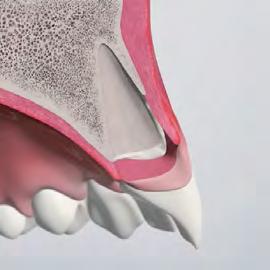

Why Gap Management Matters

While implant positioning is critical, it does not prevent post-extraction remodeling. Biomaterials play a key role in managing the peri-implant gap and maintaining long-term hard- and soft-tissue stability.

“Placing an implant does not stop facial bone remodeling. The implant is a passive occupant — reconstruction with biomaterials is required to maintain volume and long-term hard- and soft-tissue stability.”